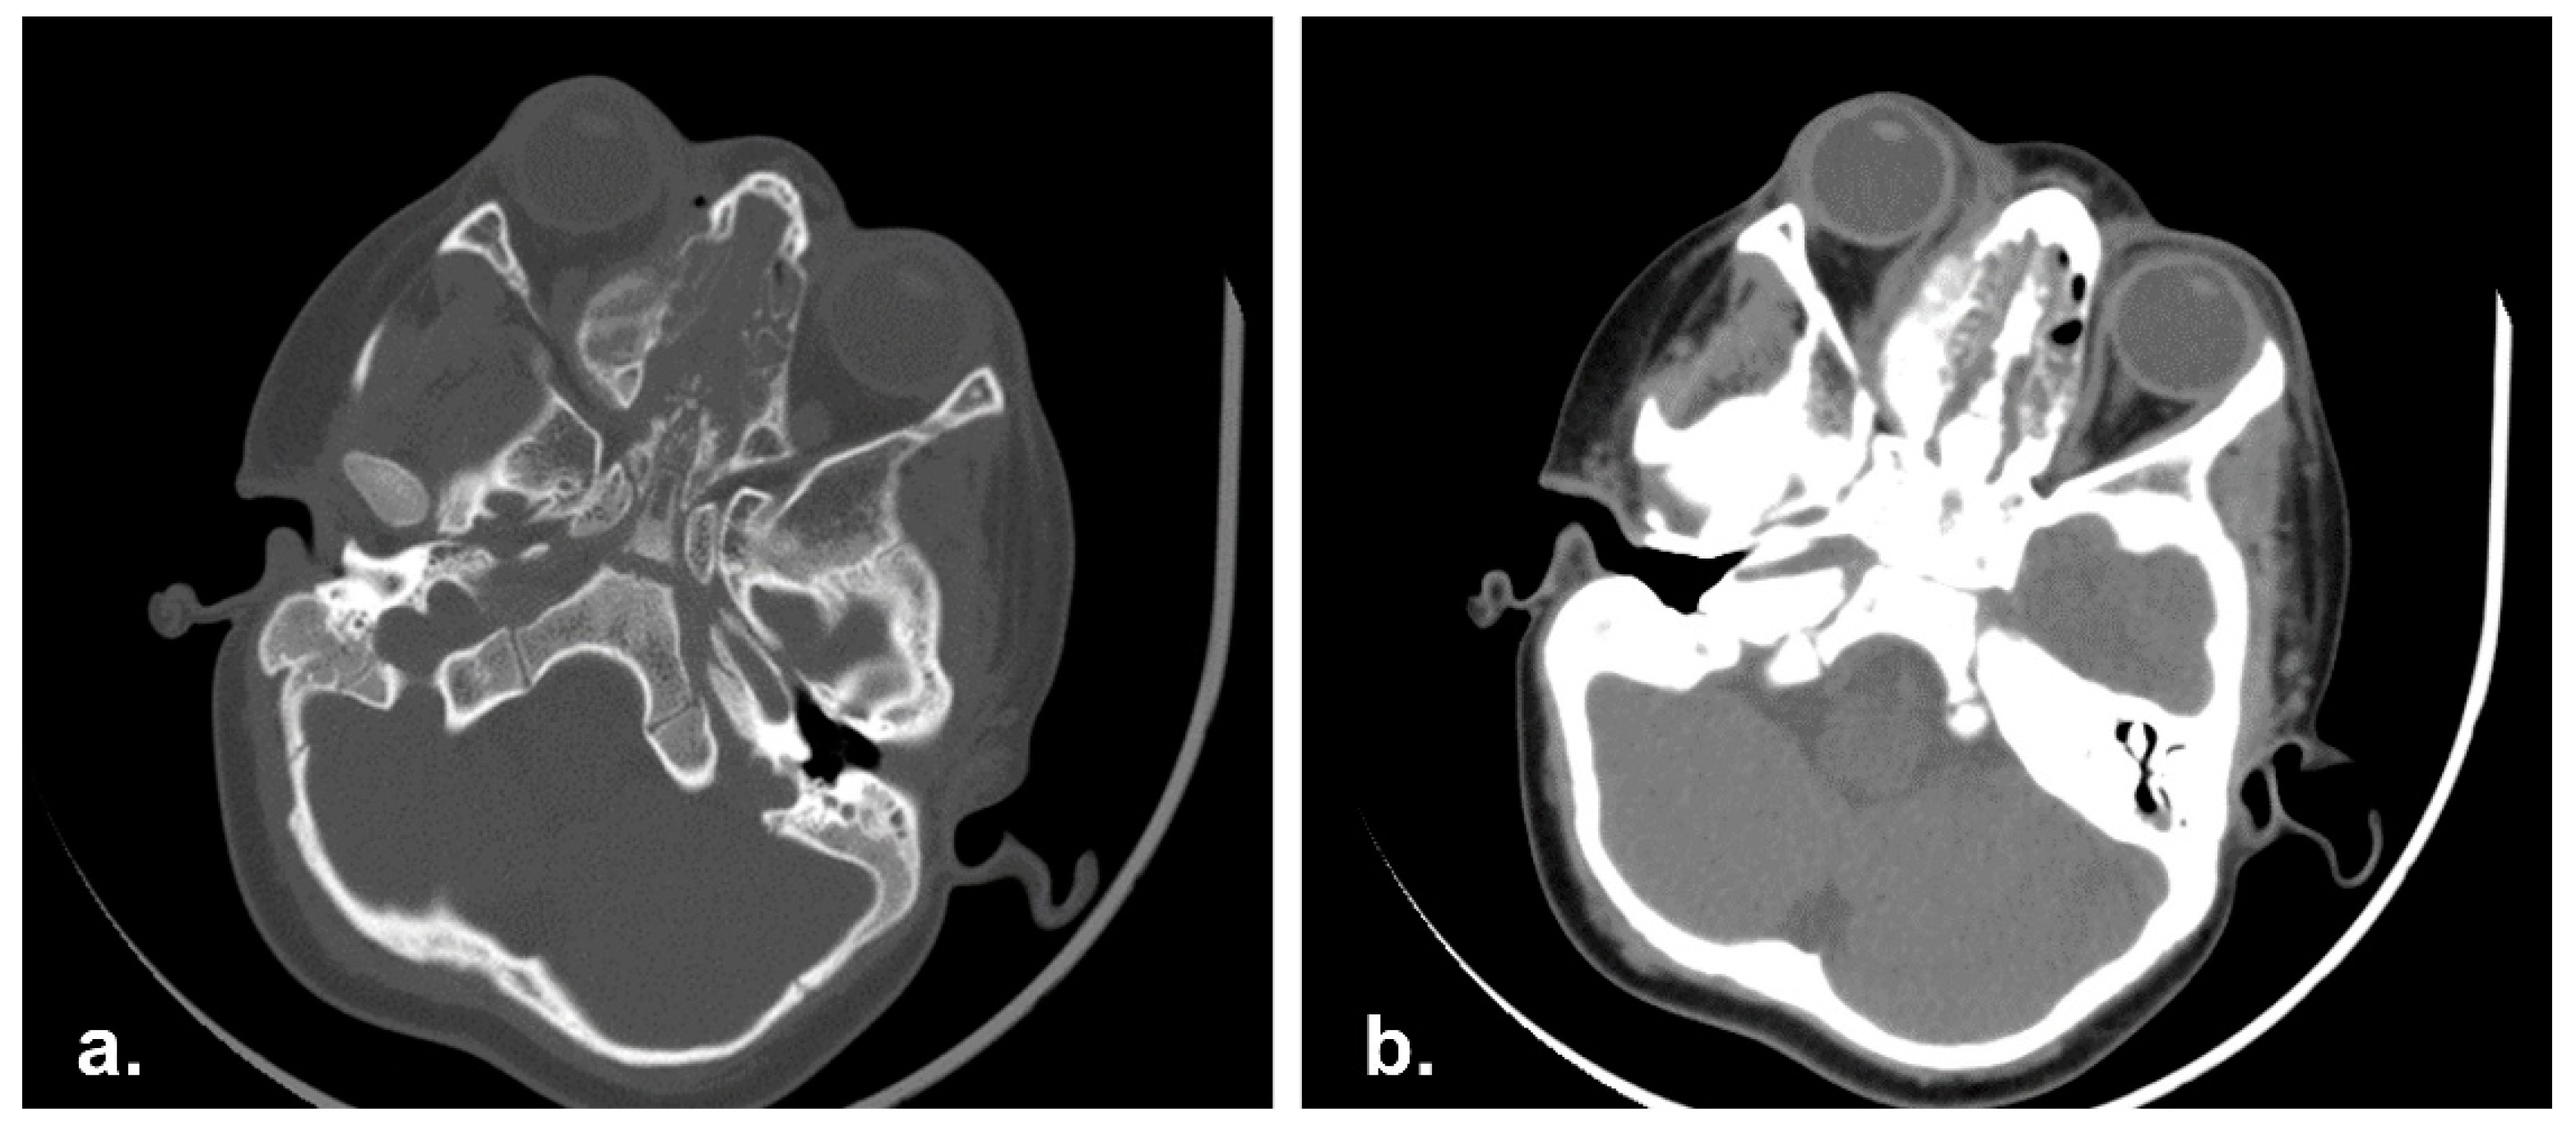

MRI showed a wide RMS (7.5 × 6 × 5 cm) involving the left masticatory space with maxillary sinus invasion. Left cheek and orbital floor were affected as well, and bilateral positive lymph nodes were detected (Figure 6).

Figure 6. Pre-operative Magnetic Resonance Imaging (MRI) in axial (a) and coronal (b) view with showing a massive neoplasia in the right masticatory space.